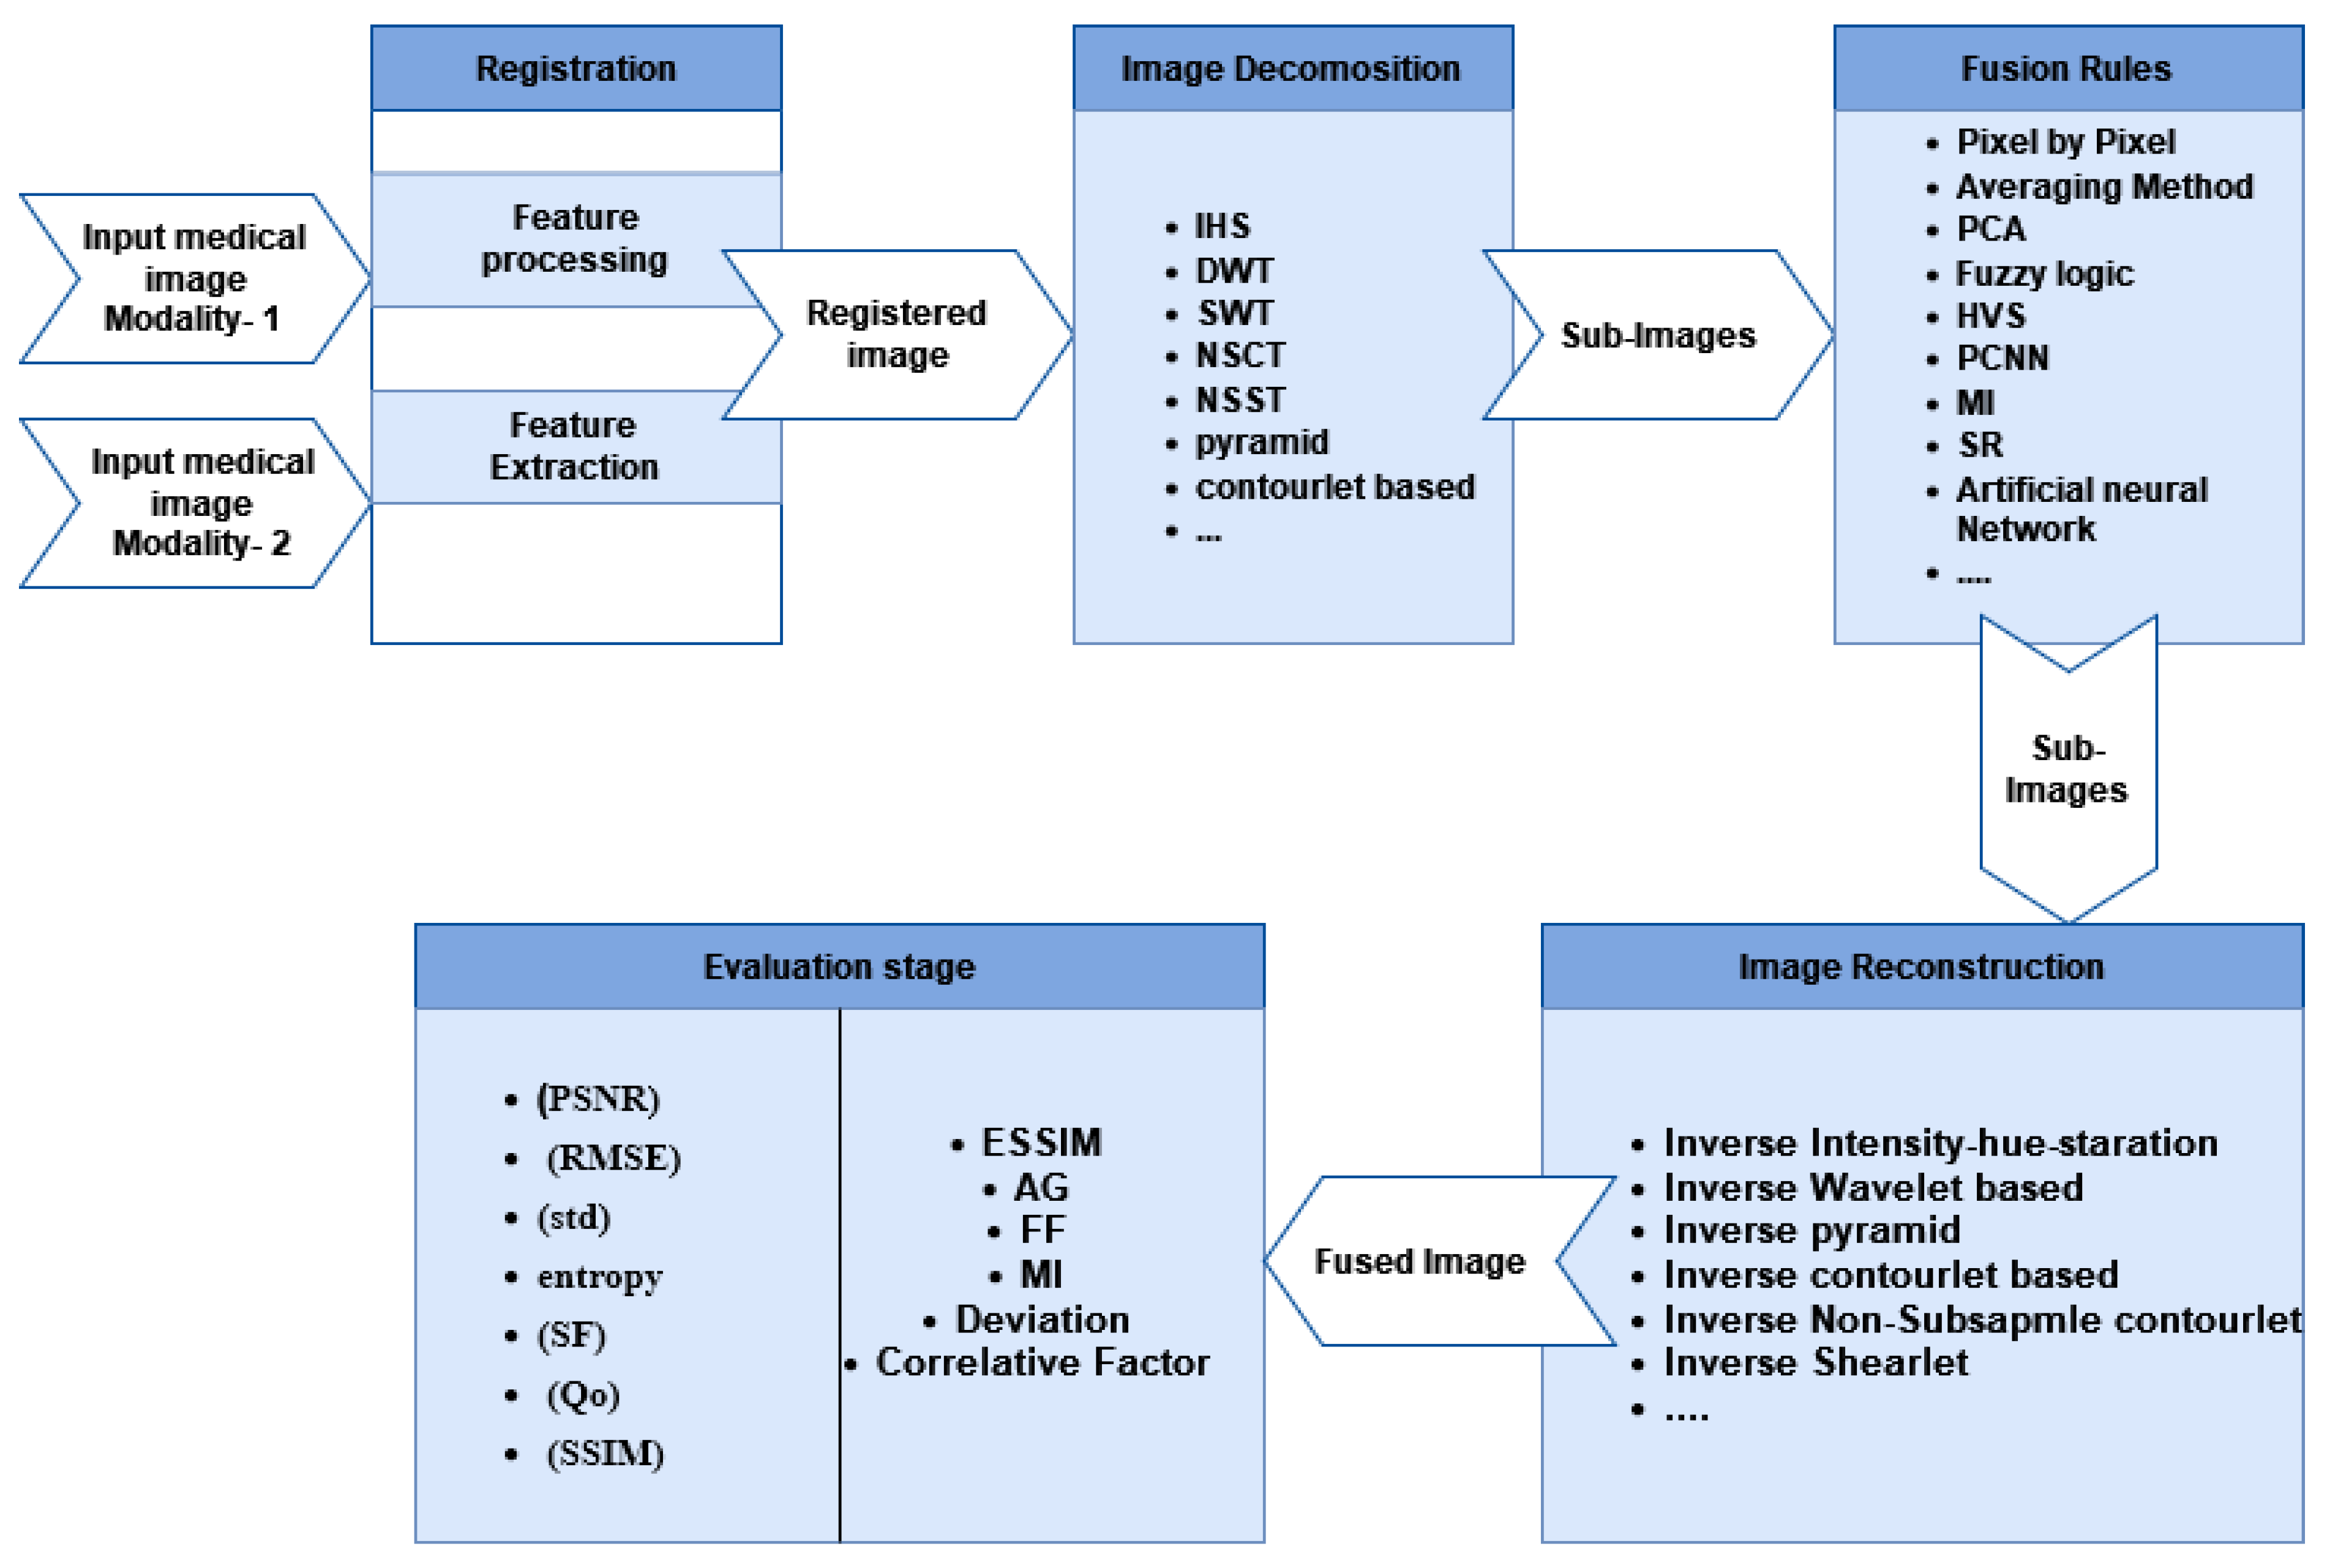

3. Fusion Steps

4. MMIF Levels